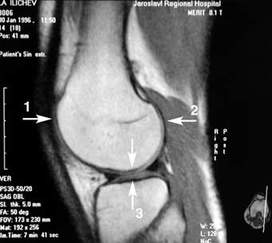

Диагностика препателлярного бурсита обычно не представляет трудностей. Диагноз ставит хирург после выявления и уточнения жалоб, анамнеза, общего осмотра. В случаях, если отек появился сразу после травмы, необходимо выполнить рентгенограмму коленного сустава для исключения костных повреждений.

При наличии инфекции в препателлярной сумке рекомендуется выполнить пункцию и последующее исследование полученной жидкости.